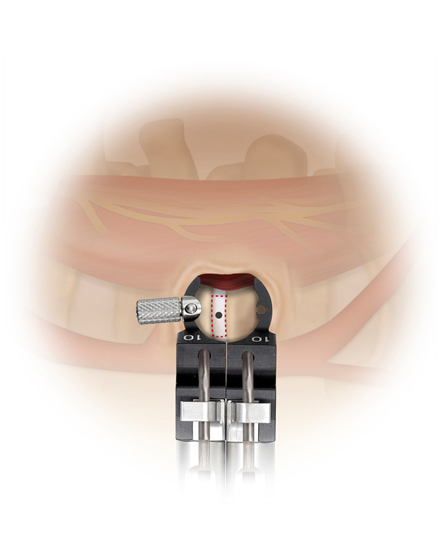

日本では2013年から承認されている低侵襲な脊椎側方固定術です。この手術は、トレーニングを受けた医師だけが実施できるため、全国でも限られた医療機関でのみ受けられます。当センターの日方医師は資格を有しているため実施可能です。この手術の最大の利点は脊髄神経を直接触らないで神経を圧迫から解除することにあります。側腹部に約5cmの皮膚切開により、下図のように神経機能を電気モニタリングで随時確認し重要な神経を避けながら椎間板内に人工骨を移植します。その後、腰部から固定術を行います。翌日から起立・歩行が許可され、入院期間は通常10~14日程度になります。